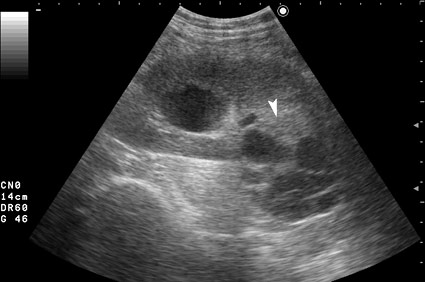

Серошкальное УЗИ. В области нижнего полюса определяется образование сложной структуры (стрелка).

Да, это был рак почки, кистозная форма. Гистология - светлоклеточный рак.